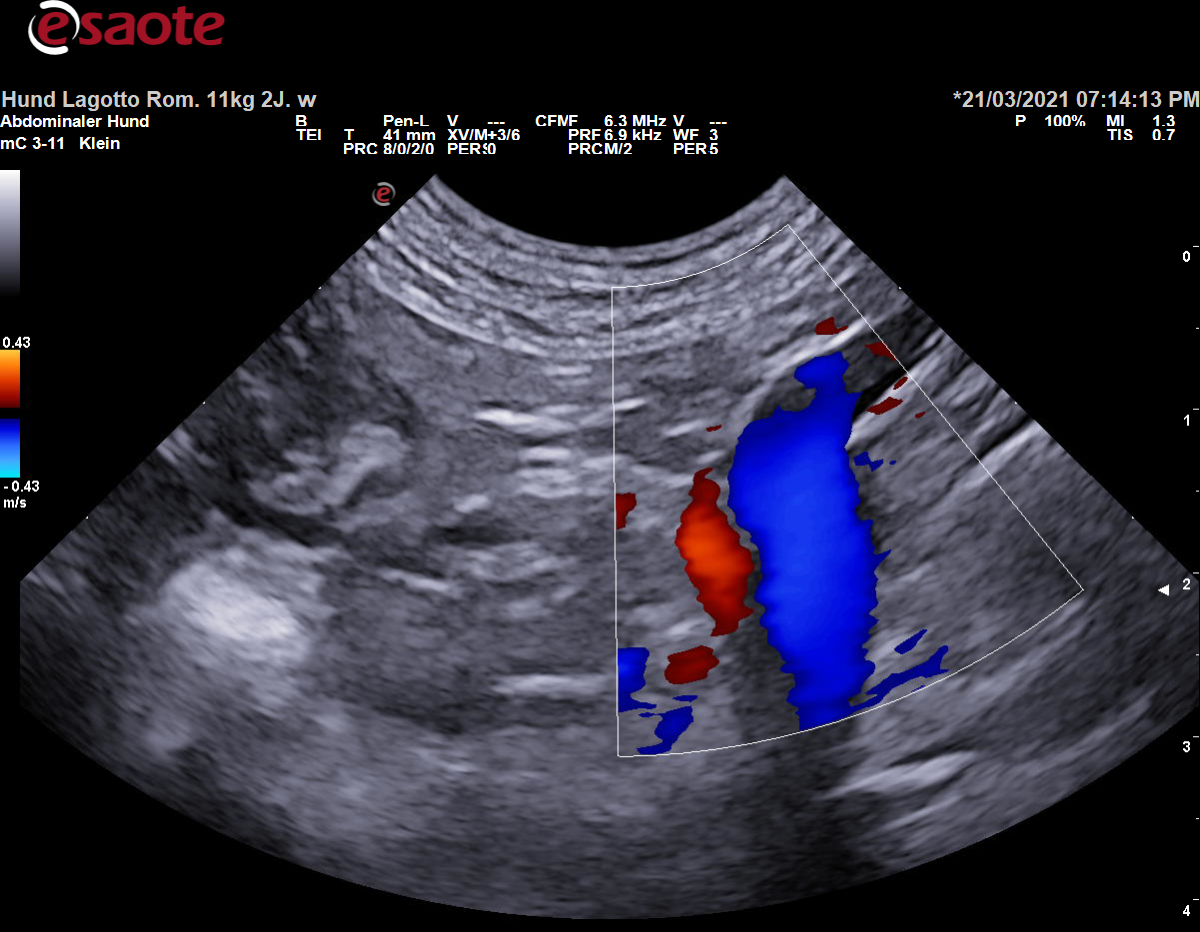

Farbdoppler:

Blutfluss in der V. portae und ihren Zuflüsse Richtung Leber (hepatopedal)

Blutfluss in den Portalvenenästen Richtung Peripherie der Leber

Blutfluss ist dadurch auf den Schallkopf zu gerichtet und wird rot kodiert

Darstellung der Vena portae im mittleren Abdomen im Farbdoppler Darstellung der Vena portae im mittleren Abdomen im Farbdoppler mit Beschriftung